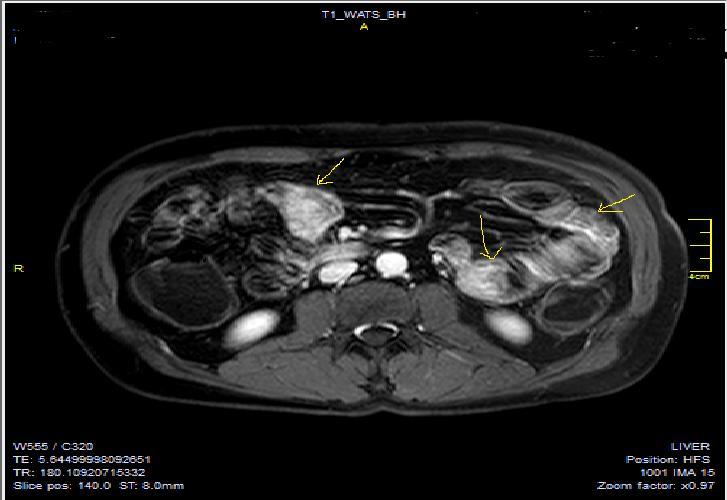

Diffusion-weighted imaging(DWI) and magnetization transfer imaging(MTI) are the new imaging sequences and techniques that can be performed for the accurate diagnosis of Crohn’s disease2, 9, 10. In case of active inflammation, restricted diffusion on high-b-value is conducted at DWI in case of Crohn’s disease, whereas infrequent for ulcerative colitis. To my experience, DWI may play a collaborating role in the imaging of patients who can’t tolerate OCA’s or in patients in whom IV contrast agent use is contraindicated5, 9.MTI may reflect the enteric fibrosis and stricture development in Crohn’s disease via transfer of energy from the free water protons inside the lumen, to the macromolecules especially for the collagen fibers at the bowel wall9, 10, 11, 12. Motility of the small intestine can be visualized by cine MRI via fast T2W images or true fast steady-state precession imaging, abnormal bowel motility and inflammatory activity in Crohn’s disease can be shown, based on wall thickness, ulceration and T2 signal intensity 9, 11, 12, 13 (Figure 1a-b).

Figure 1a.Diffuse mucosal involvement and increased wall thickness with loss of valvula conniventes in the ileal segments on T2W coronal images after OCA administration, seen on 30 years old female with moderate Crohn’s disease.

Figure 1b.Diffuse bowel wall enhancement in the small intestine due to Crohn’s disease on the Post-contrast T1W coronal sequence.